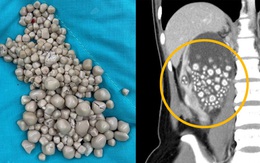

Có 300 viên sỏi thận vì uống trà sữa

Ở tuổi 20, một cô gái ở Đài Loan đã phải "trả giá" cho thói quen uống trà sữa thay nước lọc của mình, bằng 300 viên sỏi thận.